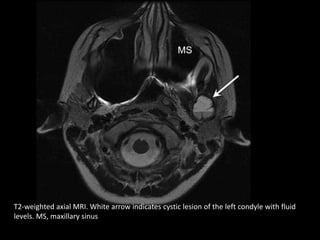

T2-weighted axial MRI. White arrow indicates cystic lesion of the left condyle with fluid

levels. MS, maxillary sinus

T2-weighted axial MRI.White arrow indicates cystic lesion of the left condyle with fluid levels. MS, maxillary sinus